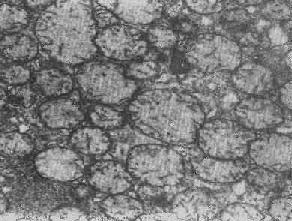

在由各种原因引起的细胞变性和坏死过程中,粗面内质网的池一般出现扩张,较轻的和局限性的扩张只有在电镜下才能窥见,重度扩张时则在光学显微镜下可表现为空泡形成,电镜下有时可见其中含有中等电子密度的絮状物。在较强的扩张时,粗面内质网同时互相离散,膜上的颗粒呈不同程度的脱失。进而内质网本身可断裂成大小不等的片段和大小泡(图1-6)。这些改变大多见于细胞水肿时,故病变不仅见于内质网,也同时累及Golgi器、线粒体和胞浆基质,有时甚至还累及溶解体。

图1-6肝细胞粗面内质网扩张 ×24000